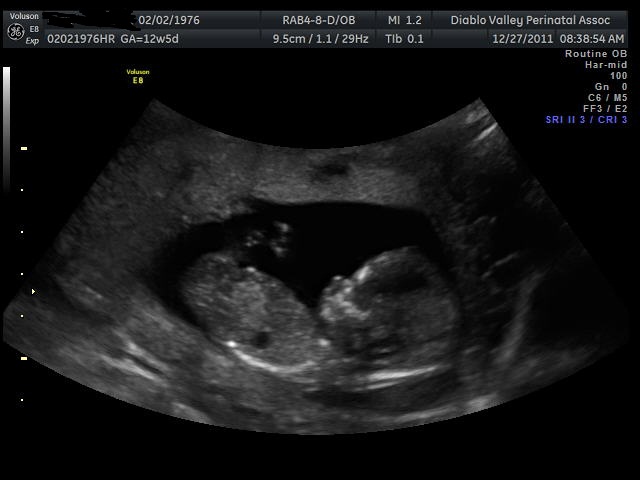

Had an elective scan today..

I can't see a clear nub in that pic, but would guess girl if I had to!

I circled what I think is the nub. Maybe that helps?

I can't see clearly either but the skull shape looks like my girl so I guess girl.

I'd say skull looks boy and nub could go either way.

Maybe girl x

I thought the skull looks boy and there is a lot going in the nub area. Cannot tell with much certainty.

Nub is circled in bottom/first picture..thanks!

I think we can see the nub further to the left than what you circled, its way too busy though for guessing so 50/50 based on this shot. Please have all my blue dust ;)